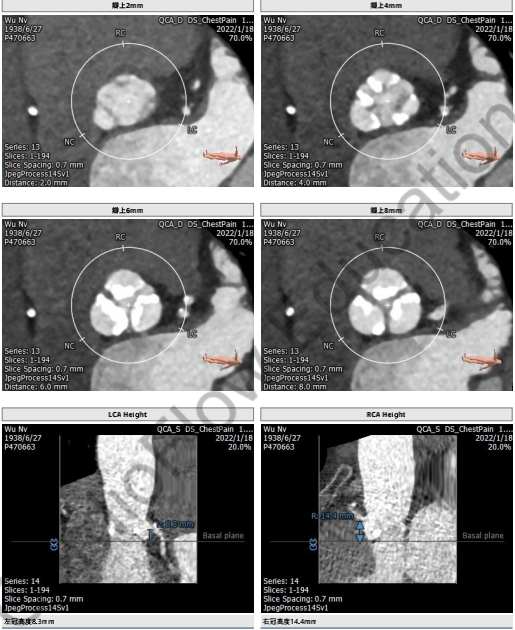

主动脉CTA:

主入路CTA:

吴伟、李荣教授团队术前总结了该病例特点:此例患者为三叶瓣重度主动脉瓣狭窄病人,瓣环72.8mm,LVOT24.0 mm,瓦式窦均径30mm,STJ 28.3mm,升主动脉41.2mm,左冠高度8.3mm,右冠高度14.4mm,下肢入路右侧血管最小径4.8mm,左侧最小径3.8mm,通过入路超声造影,显示右侧入路血管极其狭窄且重度钙化,特别是主动脉弓部钙化较重,但主动脉根部解剖形态较好,瓣叶钙化较重,考虑到球囊预扩后瓣叶可推开,由于左冠开口较低,在选择球囊型号和输送系统型号上是本次手术的关键点。